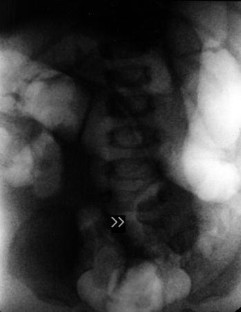

An abnormal cecum position is usually found in patients with intestinal malrotation. We report one case with intussusception and intestinal malrotation in a 10-month-old infant. An unusual radiologic imaging feature and also abnormal intussusception mass location are discussed.

Fig. 1.